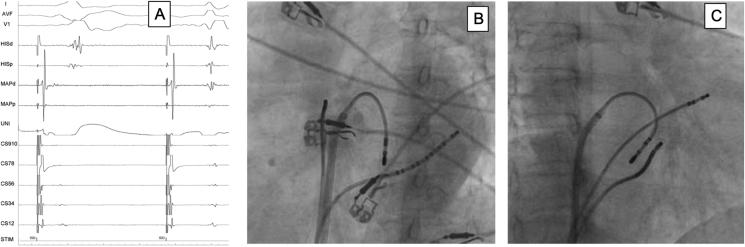

Radiofrequency ablation (RFA) has emerged as the preferred treatment modality with high success rate in cases with WPW syndrome. Arrhythmogenic complications are rarely reported after RFA, except for early or late recurrence of accessory pathway (AP) conduction. We present a unique case where the AP was successfully ablated, however, a new monomorphic PVC of similar morphology to the pre-excited beats developed within 30 min of RFA. She required medical management with sotalol to overcome her worsening symptom on follow-up. The ectopics resolved after 4 months.